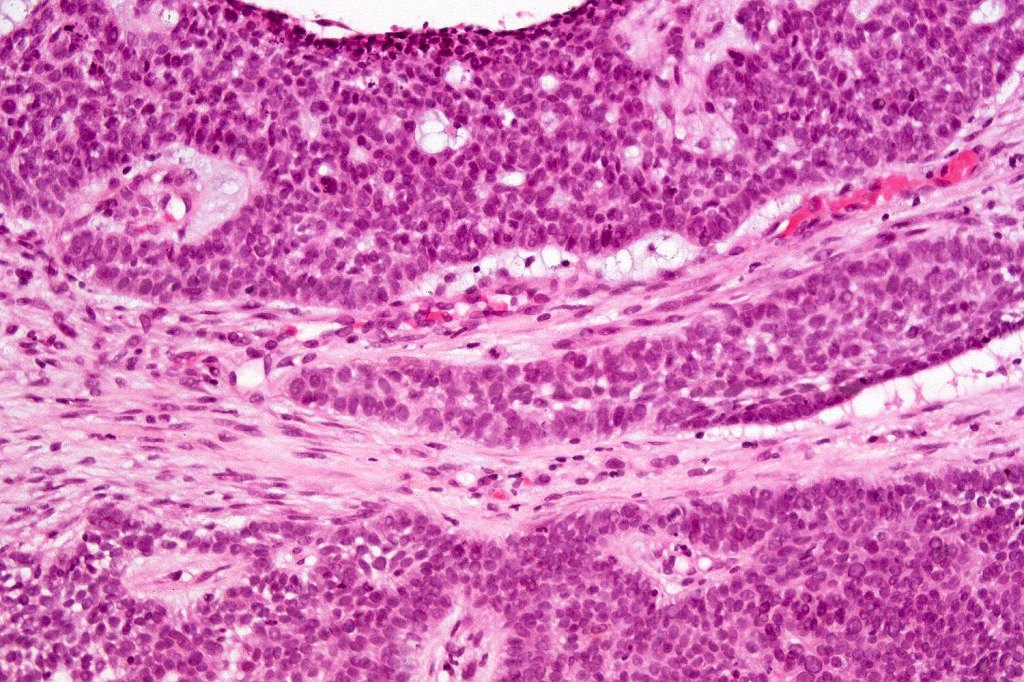

Carcinosarcoma

Cutaneous carcinosarcoma (metaplastic carcinoma, carcinoma with heterologous differentiation)

Histological features

•Osteoid

•Chondroid

•Smooth muscle

•MFH-like features with osteoclasts

•Neural differentiation